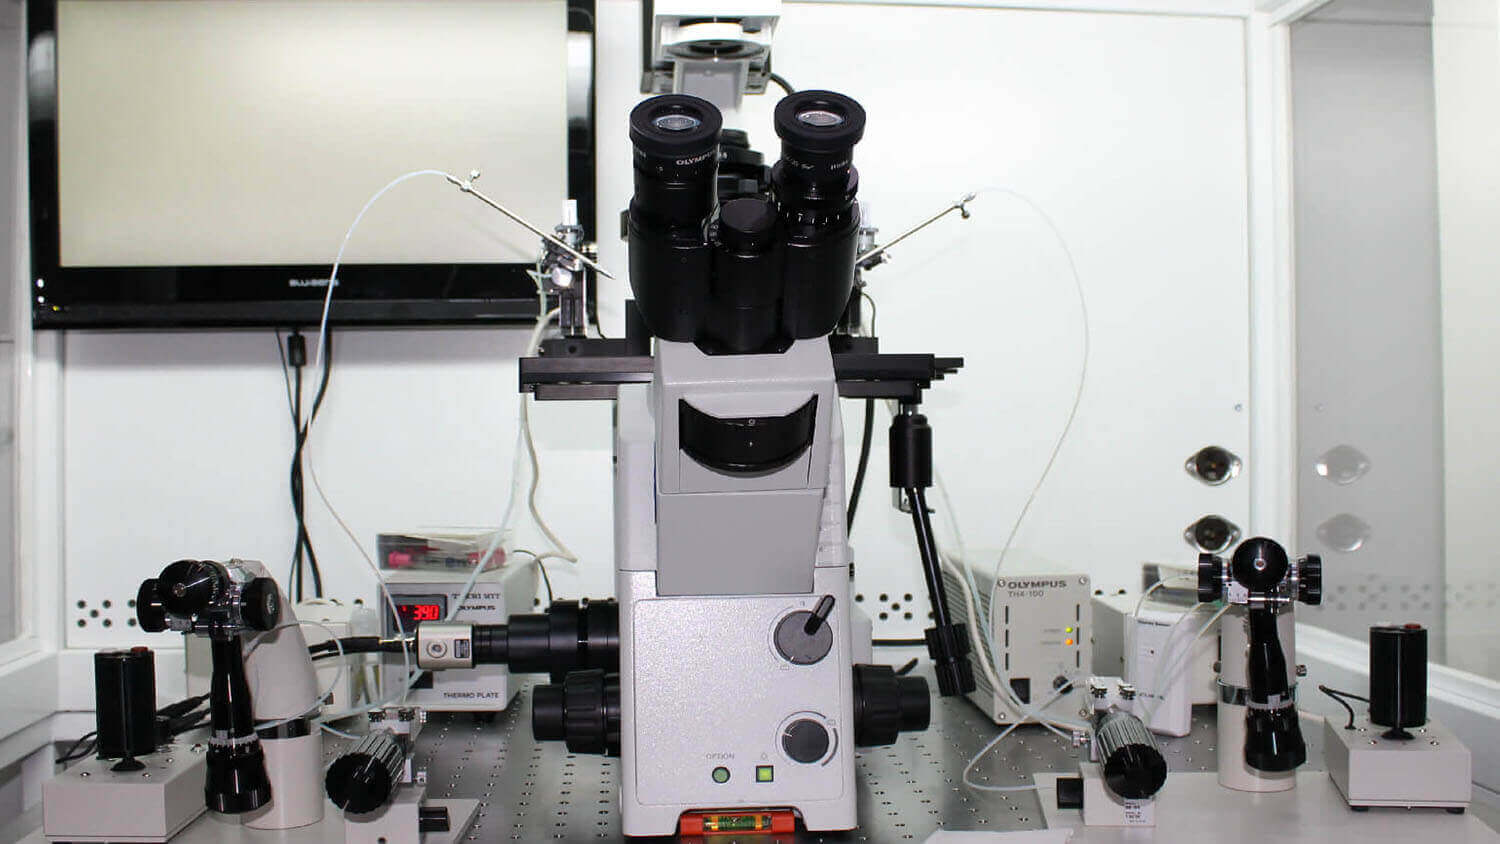

We offer the latest tchnology in our extensive experience in the following treatments:

We offerthe highest reproductive technology

in our centers.